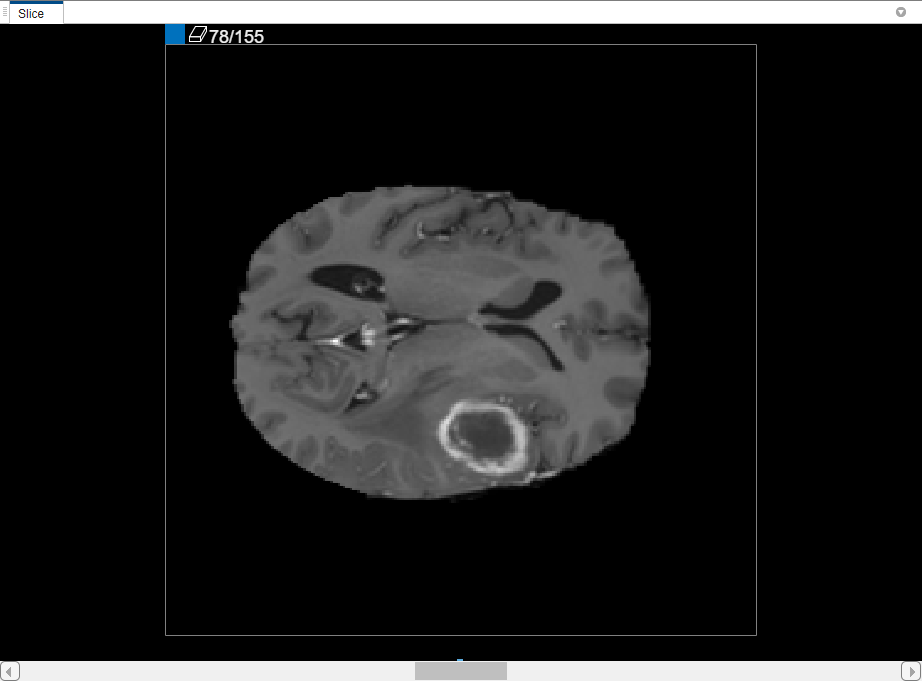

また、[スライス] ペインでボリュームの各スライスを表示することもできます。スライス間を移動するには、ペインの下部にあるスライダーを使用します。腫瘍はスライス 35 からスライス 88 で確認できます。既定の設定では、[スライス] ペインに X-Y 軸に沿ってボリュームが表示されますが、これは [領域分割] タブのツールストリップの [向き] セクションにあるボタンを使用して変更することができます。また、[スライス] ペインでは、描画ツールを使用してマスクを定義します。

内挿の使用後、個々のスライスをチェックして、満足できる ROI が作成されているかを確認します。スライス 71 では、セグメント化するオブジェクト全体が ROI で塗りつぶされていないことに注目してください。[ペイント ブラシ] ツールを使用することで、ROI を手動で調整できます。あるいは、[自動化] タブのツールのいずれかを使用することもできます。たとえば、[動的輪郭] を使用して、腫瘍の全体が塗りつぶされていないスライスで ROI を大きくすることができます。また、[アルゴリズムの追加] を使用して、ROI 上で動作する独自のアルゴリズムを指定することもできます。